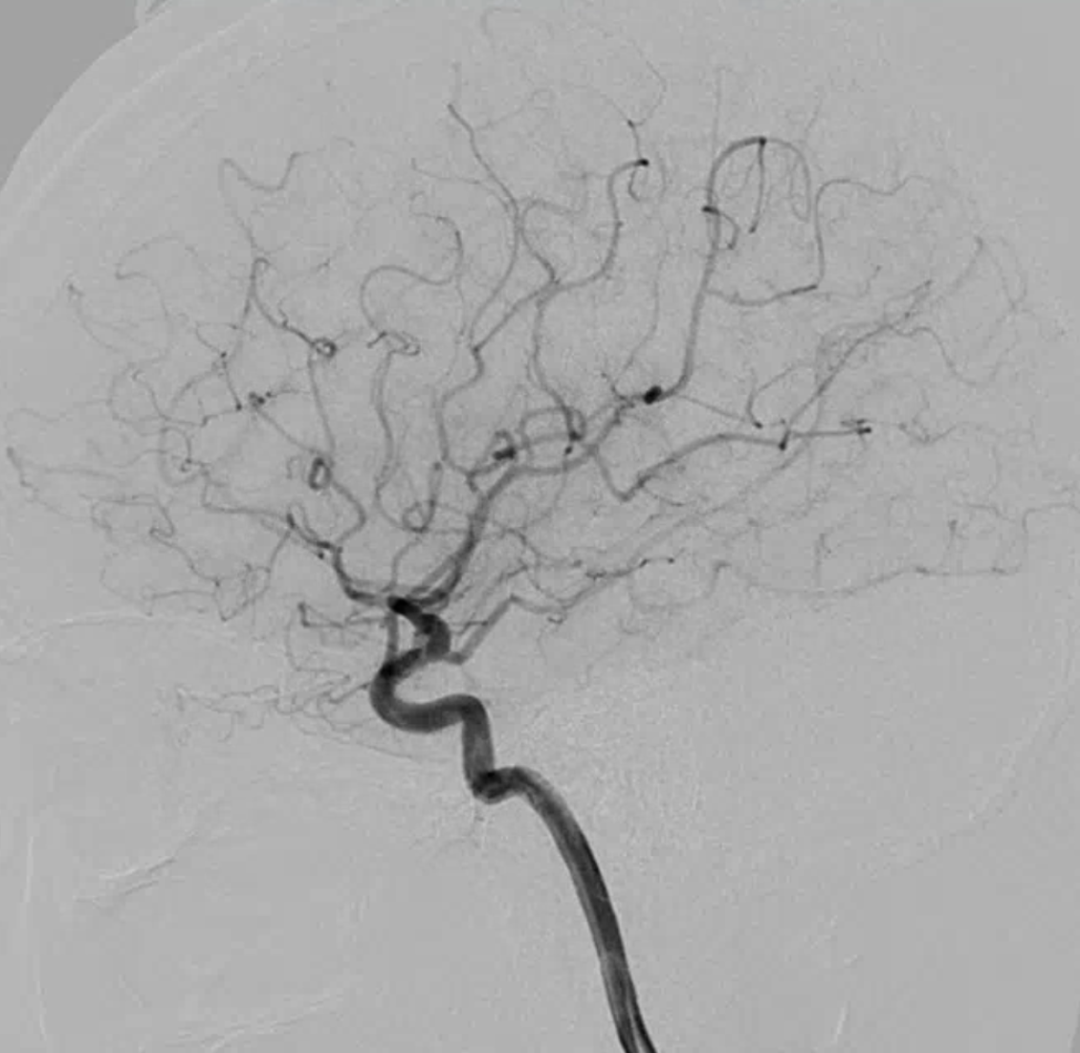

右侧颈动脉造影

左侧颈动脉造影

左侧瘤体形态欠规则,4mm×30mm Streamline 优先处理左侧动脉瘤

术后3月复查,瘤体未见显影,载瘤动脉通畅

同期4mm×20mm Streamline 进一步处理右侧动脉瘤